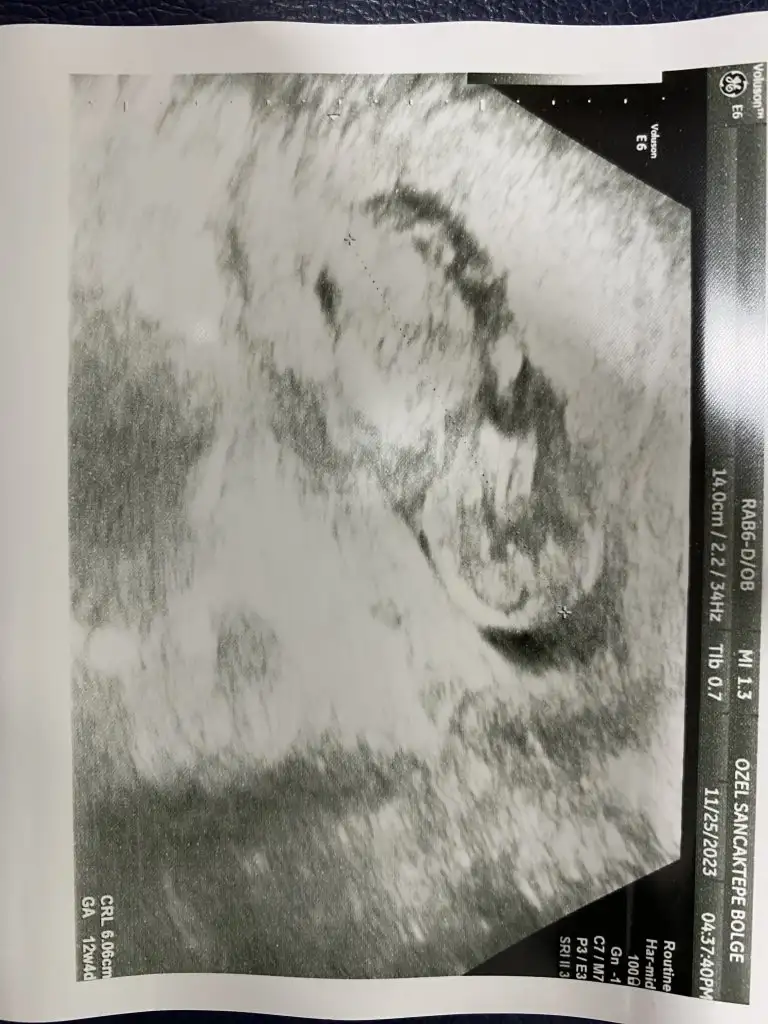

Erkek dedıgınde pipiyi gosterdımıGünaydın kızlar 16 haftalık gittim yüksek ihtimalle erkek dedi pipisini gösterdi 21 haftalık yüzde 70 kız dedi aklım çok karışık bı bakın ne olur tahminleriniz nedir

Evet gösterdi bende gördümErkek dedıgınde pipiyi gosterdımı![]()

Çok net erkek keşke benimki böyle net olsaKızlar sizce bu minik yaramaz kızmı erkekmiEki Görüntüle 3344820